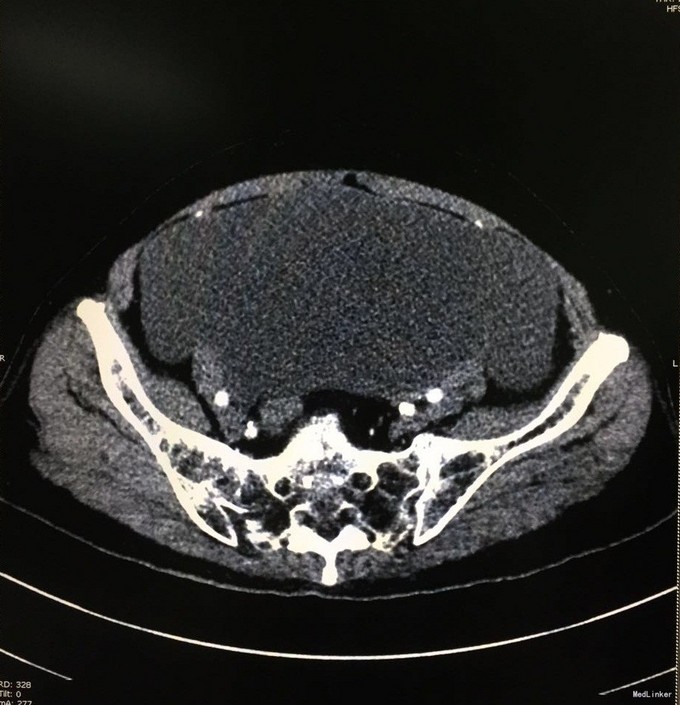

查体:腹膨隆,可及一包块,质中,活动可,边缘不清,位置较固定,无红肿热痛,无压痛。 辅查:我院CT:盆腔巨大囊性肿块,大小约15x10cm,考虑附件来源恶性肿瘤,囊腺癌可能;肝内一结节状稍低密度影,增强后轻度强化,转移瘤可能;胆囊多发结石;盆腹腔积液。肿瘤标志物:CEA:33.2U/mL。

入院诊断:腹腔肿物、胆囊结石、腹水。入院后行剖腹探查术,术中见腹腔大量胶冻样物约5000ml,左卵巢见一20x20cm囊性包块,包膜不完整,可见破溃口,内含胶冻样物,右附件及子宫未见明显异常。阑尾见3x3cm大小的粘液样肿块,腹膜、大网膜、肠管表面均有胶冻样物覆盖。遂行腹式双附件切除术+回盲部肿物切除术+腹膜活检术。术中冰冻病理示:左卵巢粘液囊腺瘤,局部增生活跃。术后病理示:左卵巢粘液性囊腺瘤,阑尾低级别粘液性腺瘤。术后诊断:左卵巢粘液性囊腺瘤并自发破裂,阑尾低级别粘液性腺瘤,胆囊结石。